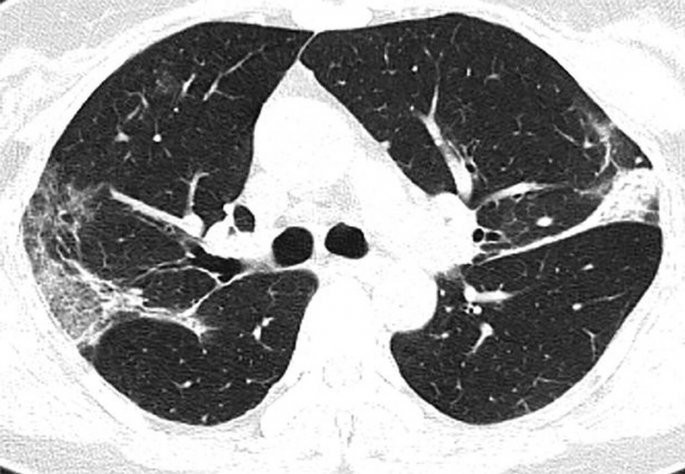

Κορωνοϊός: Ανατριχιαστική ακτινογραφία ασθενούς